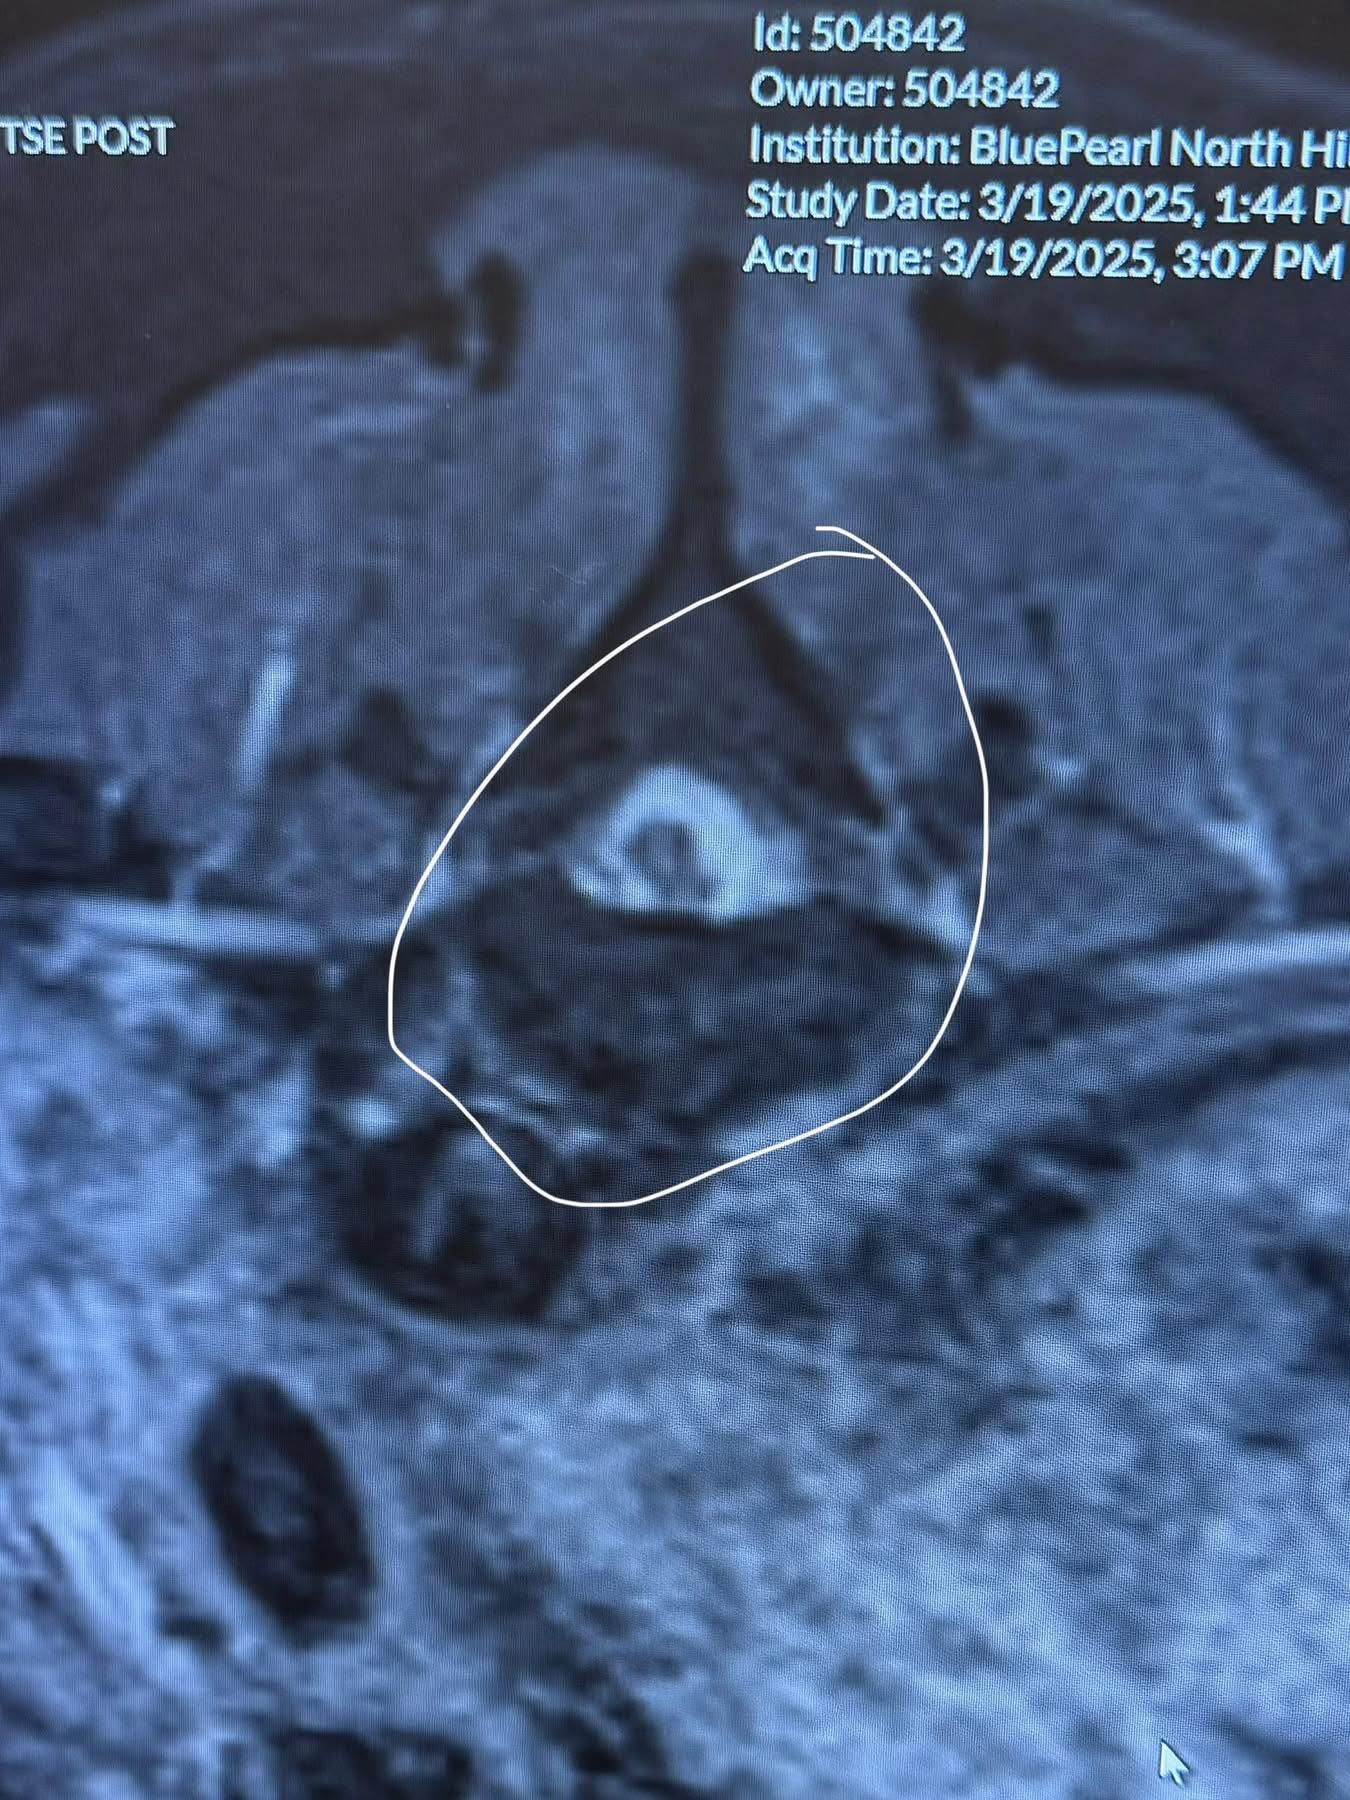

Clover has a tumor around her spinal cord, between T11 & T12 vertebrae. Basically right in the middle of her spine. In the MRI photos below, the third photo shows normal spinal cord looking at it as though you sliced into a pumpkin roll. The fourth photo shows the area the tumor is compressing on her spine. The fifth photo is the tumor itself.

Her spinal tap didn’t provide much additional information, but the best guess currently is that it is malignant, and is a plaque meningioma.